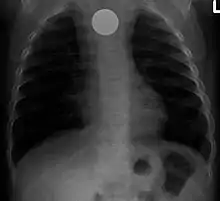

عملة نقدية تظهر في أشعة للصدر

قناة الهضم هي أبرز الأماكن التي يمكن أن نجد فيها أجساما غريبة.